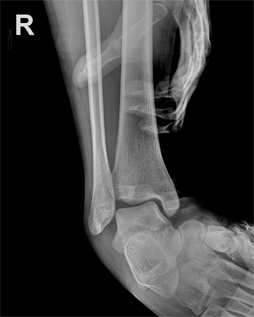

외측 불안정성 수술 전